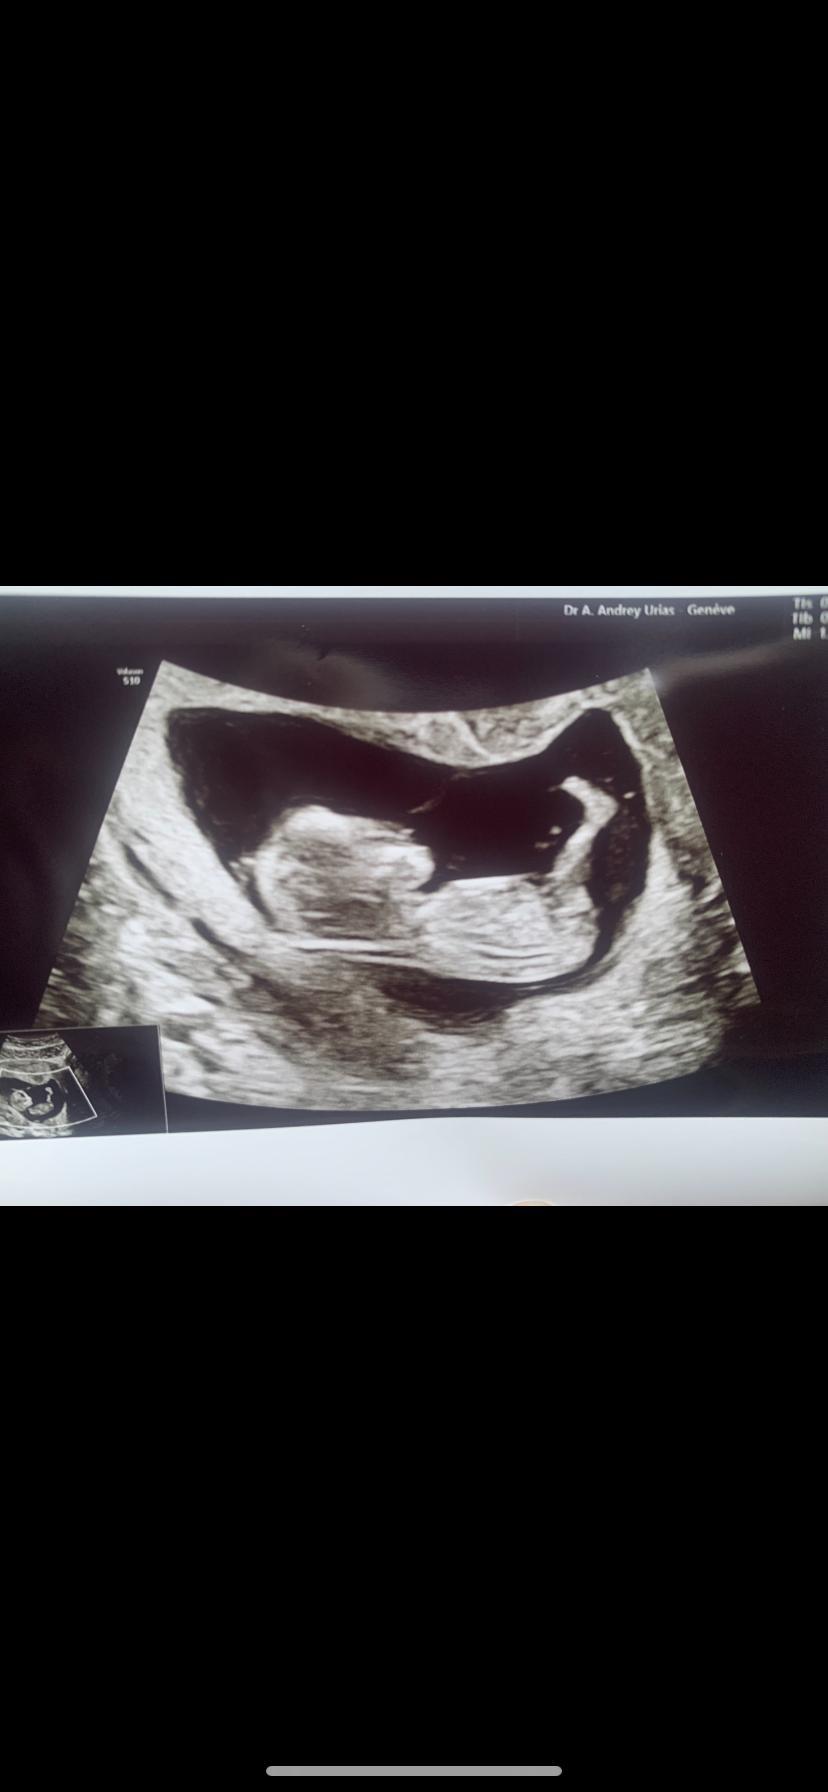

AnonymBruker Skrevet 13. oktober 2020 #1 Skrevet 13. oktober 2020 Uke 13. Hva tror dere? Har sjekket nub theory, men finner ikke nuben🤣 Anonymkode: 4f002...529

AnonymBruker Skrevet 13. oktober 2020 #4 Skrevet 13. oktober 2020 Oj, kan de ligge sånn?? 😂 med bena rett ut? jeg trodde de alltid lå i fosterstilling jeg, siden det kaller foster stilling....... 🤦🏼♀️ De har jo skikkelig god plass til å strekke seg skikkelig ut Anonymkode: 9a147...ae0 1

AnonymBruker Skrevet 13. oktober 2020 #5 Skrevet 13. oktober 2020 Ser du nuben? Hvor? Anonymkode: 4f002...529

AnonymBruker Skrevet 13. oktober 2020 #6 Skrevet 13. oktober 2020 Er ikke noe nub her. Anonymkode: 30085...098 1

AnonymBruker Skrevet 13. oktober 2020 #9 Skrevet 13. oktober 2020 Må man ikke se det fra en annen vinkel for å kunne se det? 🤔 Anonymkode: de698...782 3

AnonymBruker Skrevet 13. oktober 2020 #10 Skrevet 13. oktober 2020 Den ligger på siden jo, synes ingenting. Anonymkode: 0fc92...f3b 2

AnonymBruker Skrevet 13. oktober 2020 #11 Skrevet 13. oktober 2020 Dette er tvillinger! Grattis! Anonymkode: 62438...5b6 6

AnonymBruker Skrevet 13. oktober 2020 #17 Skrevet 13. oktober 2020 Det er jo en gutt! Men hvor er beina? Anonymkode: f9a11...11a